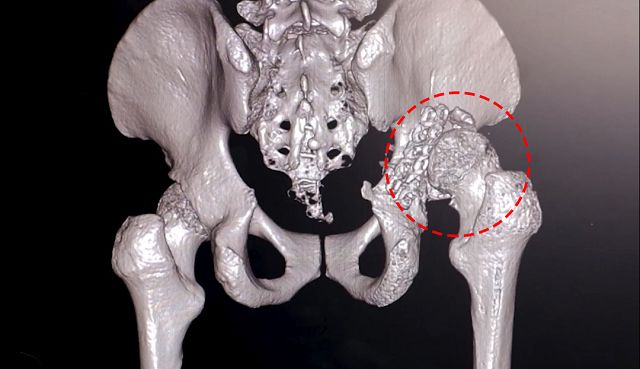

光田綜合醫院骨科部長李芳材檢查,發現病人髖關節已經嚴重損壞位移失去功能,而且長期錯位、加速軟骨磨損造成關節疼痛與長短腳,同時也壓迫病人坐骨神經,造成右腳麻痛難耐,以及更糟的右腳板垂足,讓他無法舉步行走。

為讓男大生恢復走路重拾生活品質,李芳材、楊鎮源協同關節重建科主任蕭敬樺共同擬定手術計畫。蕭敬樺醫師解釋,首先為病人置換人工髖關節考量其髖關節因錯位有嚴重骨缺損,髖臼就像破了洞的碗,醫師透過院內骨骼銀行異體骨移植填補破洞後,再置換人工髖關節到正確位置,讓髖關節恢復功能同時也一併改善長短腳。